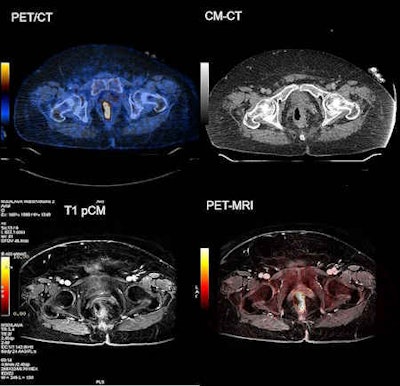

Left-sided, FDG-avid rectal cancer with rectal wall thickening. Note the improved detectability of the surrounding infiltration and detectability of the small locoregional lymph node. Images courtesy of Dr. Veit-Haibach.

Left-sided, FDG-avid rectal cancer with rectal wall thickening. Note the improved detectability of the surrounding infiltration and detectability of the small locoregional lymph node. Images courtesy of Dr. Veit-Haibach.After the board is positioned over the scanner table, the table is elevated until it supports the board. The board is released from the sliding arms and the images are acquired. Upon completion of the exam, the shuttle is positioned next to the scanner table and the arms are slid underneath the transport board. When the scanner table is lowered, the patient is transferred back onto the shuttle.